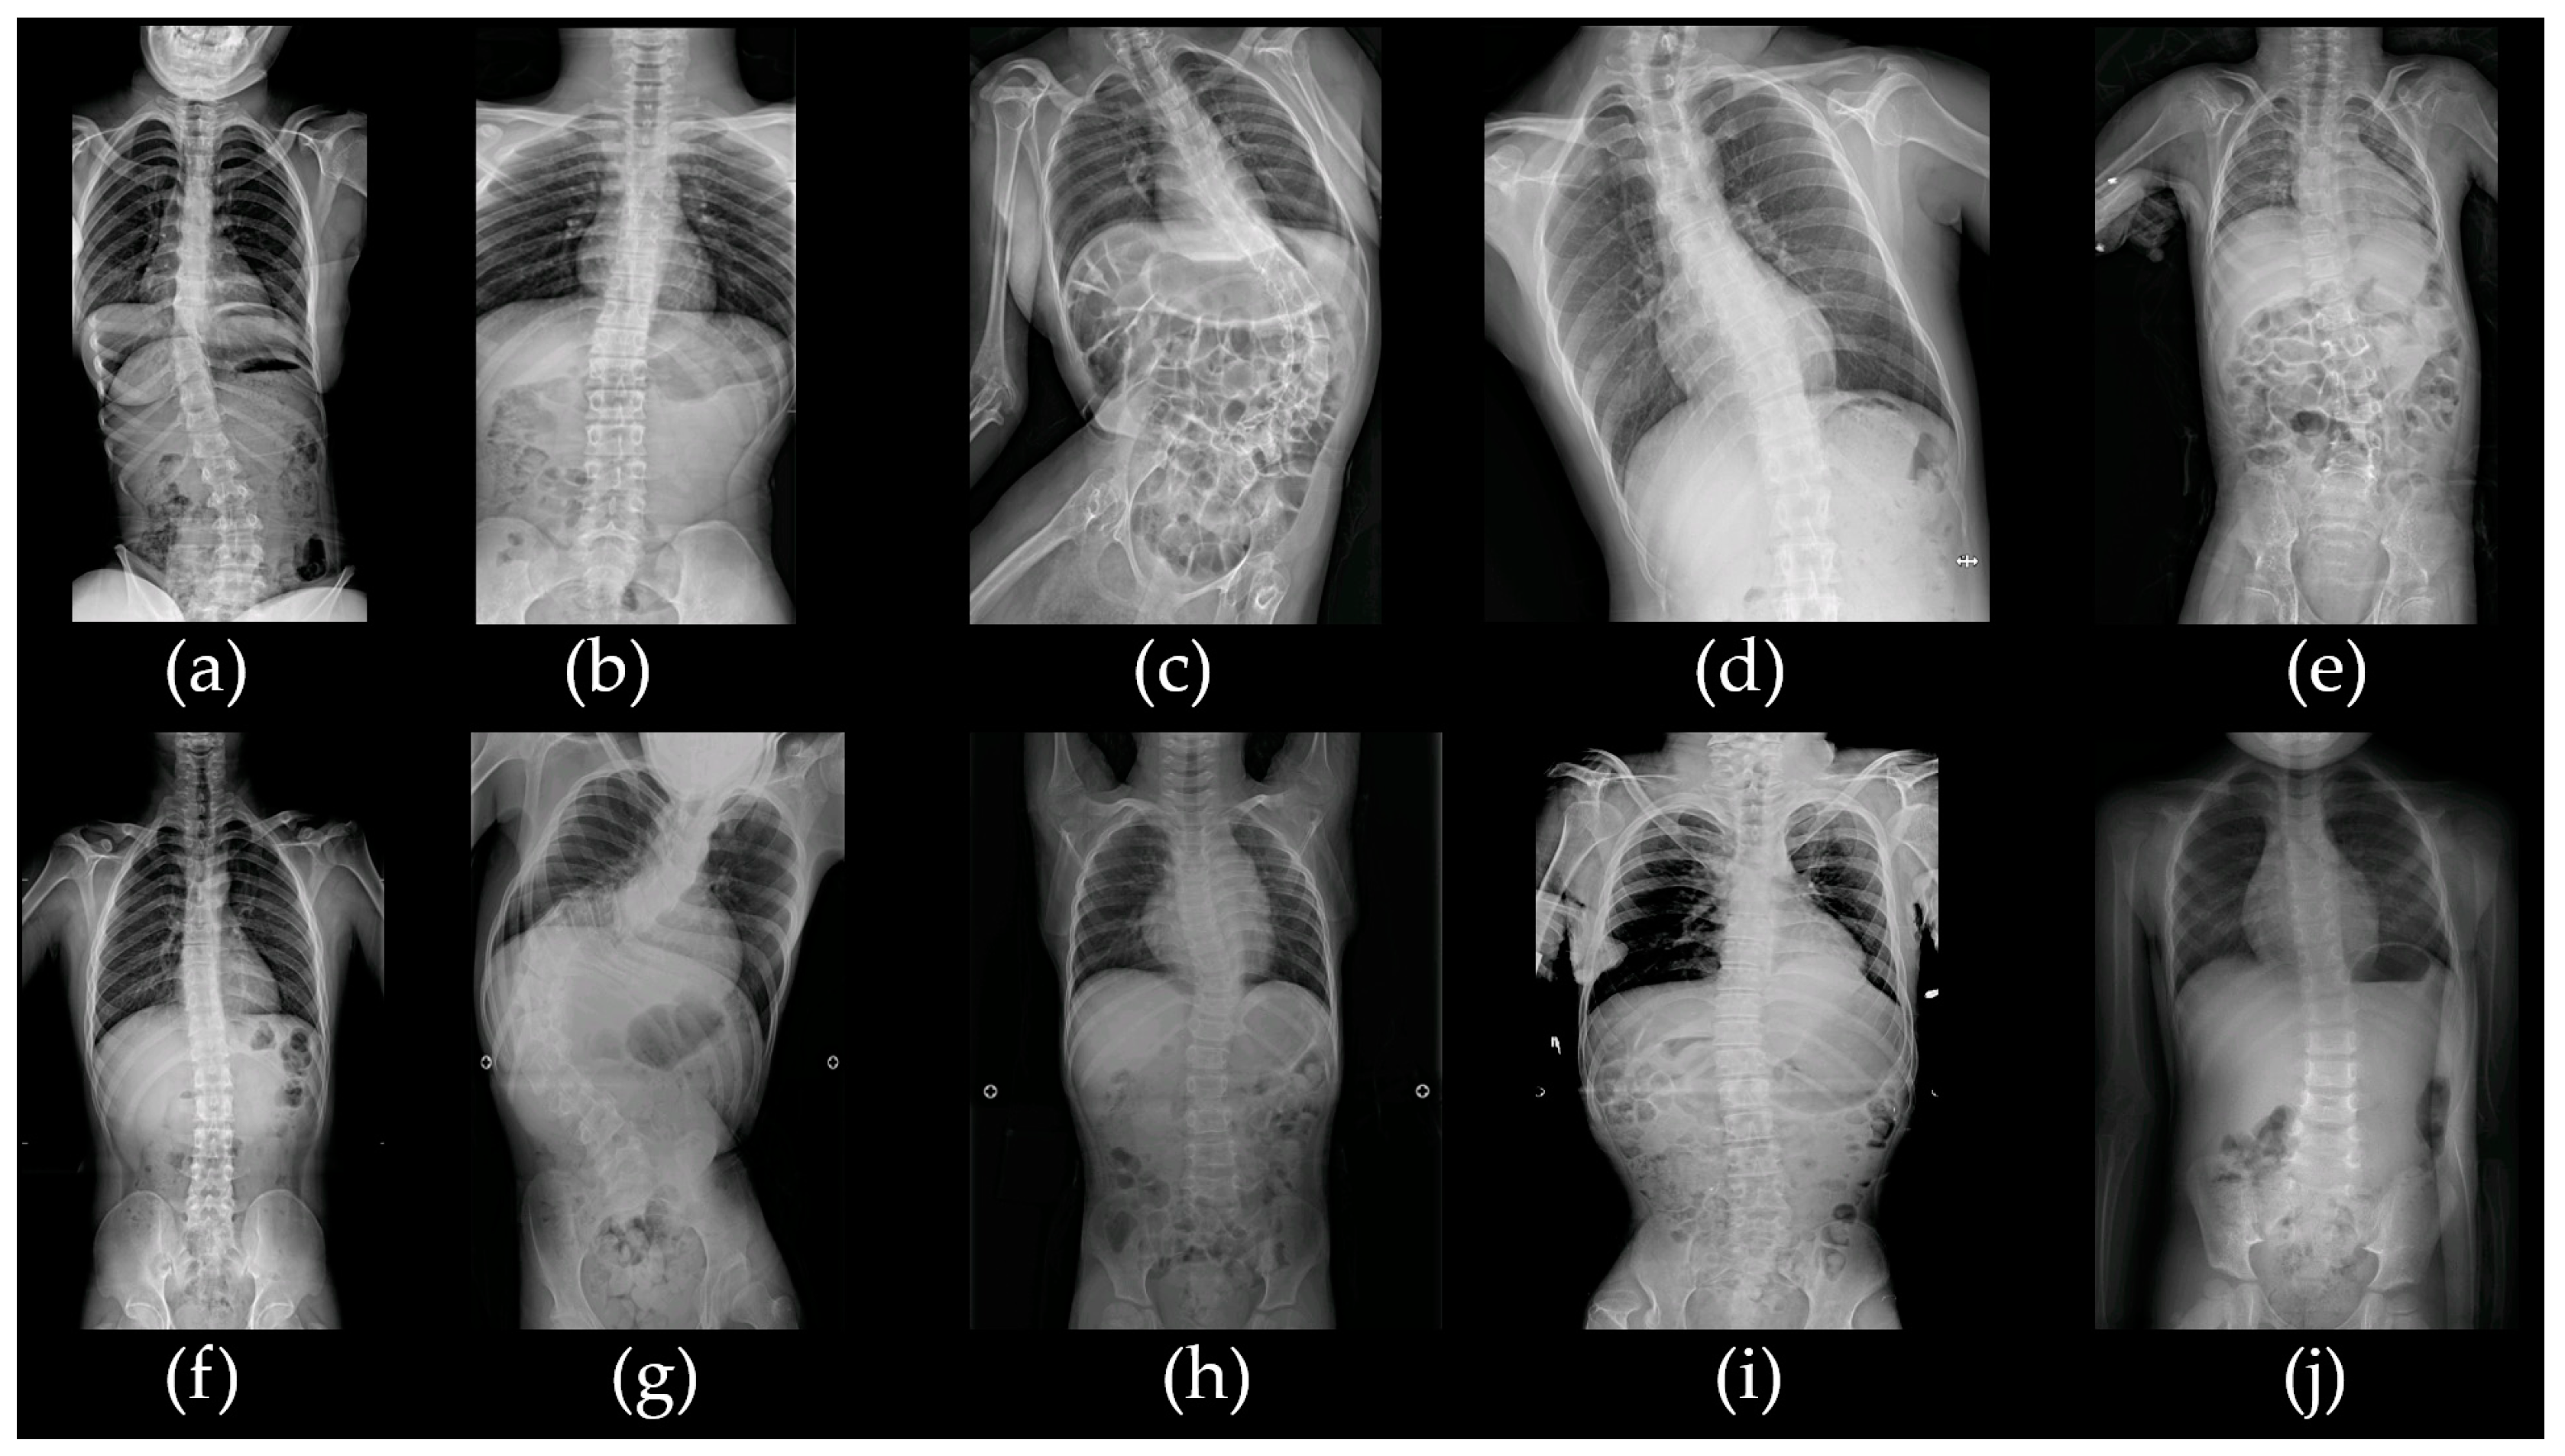

| Patient | S/A (y) | GA/BW | CP Types | GMFCS | ID | Epi/OA | Other Comorbidities | Brain MRI |

|---|---|---|---|---|---|---|---|---|

| acp01k | F/13 | 38 wks/3 kg | SQ | V | Profound | +/1 mo | NH, microcephaly | Normal |

| acp02s | M/21 | 29+5 wks/1.42 kg | SQ | V | Severe | +/20 y | None | Periventricular leukomalacia (grade II) |

| acp03k | F/15 | 38 wks/3 kg | SQ | V | Profound | +/12 mo | None | Frontotemporal atrophy with demyelinating changes |

| acp04m | F/39 | 38 wks/3 kg | Athetoid | II | Normal | −/− | None | Normal |

| acp05y | M/9 | 36 wks/2.5 kg | SQ | V | Profound | +/2 mo | None | Schizencephaly with associated callosal agenesis, hydranencephaly |

| acp06l | M/18 | 40 wks/3.36 kg | SD | V | Severe | −/− | NH | Normal |

| acp07l | M/20 | 37 wks/2.9 kg | SQ | V | Profound | +/16 y | NH | Normal |

| acp08p | M/17 | 33 wks/2.56 kg | SQ | V | Profound | −/− | NH, cryptorchidism, facial dysmorphism, thin and long fingers | Widening of the side ventricles |

| acp09k | M/25 | 41 wks/3 kg | SQ | V | Profound | +/25 y | NH, cleft palate | Schizencephaly with cortical dysplasia |

| acp10k | F/8 | 39 wks/3.5 kg | SD | III | Mild | +/7 y | SNHL, ataxia | Normal |